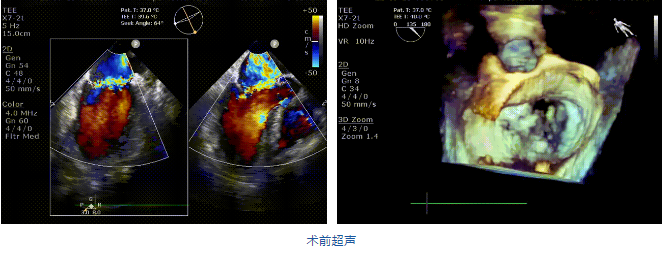

接受治療的是一例二尖瓣重度反流的患者,主訴“突發(fā)間歇性胸悶,氣急6天”。術(shù)前超聲提示:1.二尖瓣脫垂伴重度關(guān)閉不全(瞬時量30ml);2.左心、右房增大(左房容積110ml,左室容積129ml,右房容積55ml);3.左室收縮功能正常。患者在充分標(biāo)準(zhǔn)化藥物治療后(GDMT)仍然癥狀明顯,韓林教授及其團隊唐楊烽教授,以及心超科的周廣為醫(yī)生決定使用我國創(chuàng)新器械JensClip為患者進行二尖瓣緣對緣修復(fù)手術(shù)。

在阜外醫(yī)院潘湘斌教授團隊的支持下,手術(shù)經(jīng)股靜脈-房間隔入路,采用全身麻醉插管,在TEE和DSA引導(dǎo)下完成房間隔穿刺。置入JensClip瓣膜夾系統(tǒng)后,在左房調(diào)整瓣膜夾的位置和軸向,后進入左室,在TEE引導(dǎo)下捕捉二尖瓣前后瓣葉,并關(guān)閉瓣膜夾。經(jīng)TEE反復(fù)確認(rèn)手術(shù)效果后最終鎖定并釋放瓣膜夾。術(shù)后即刻超聲顯示瓣膜夾位置穩(wěn)定,功能良好,二尖瓣反流由術(shù)前4+減少至微量,手術(shù)圓滿成功。